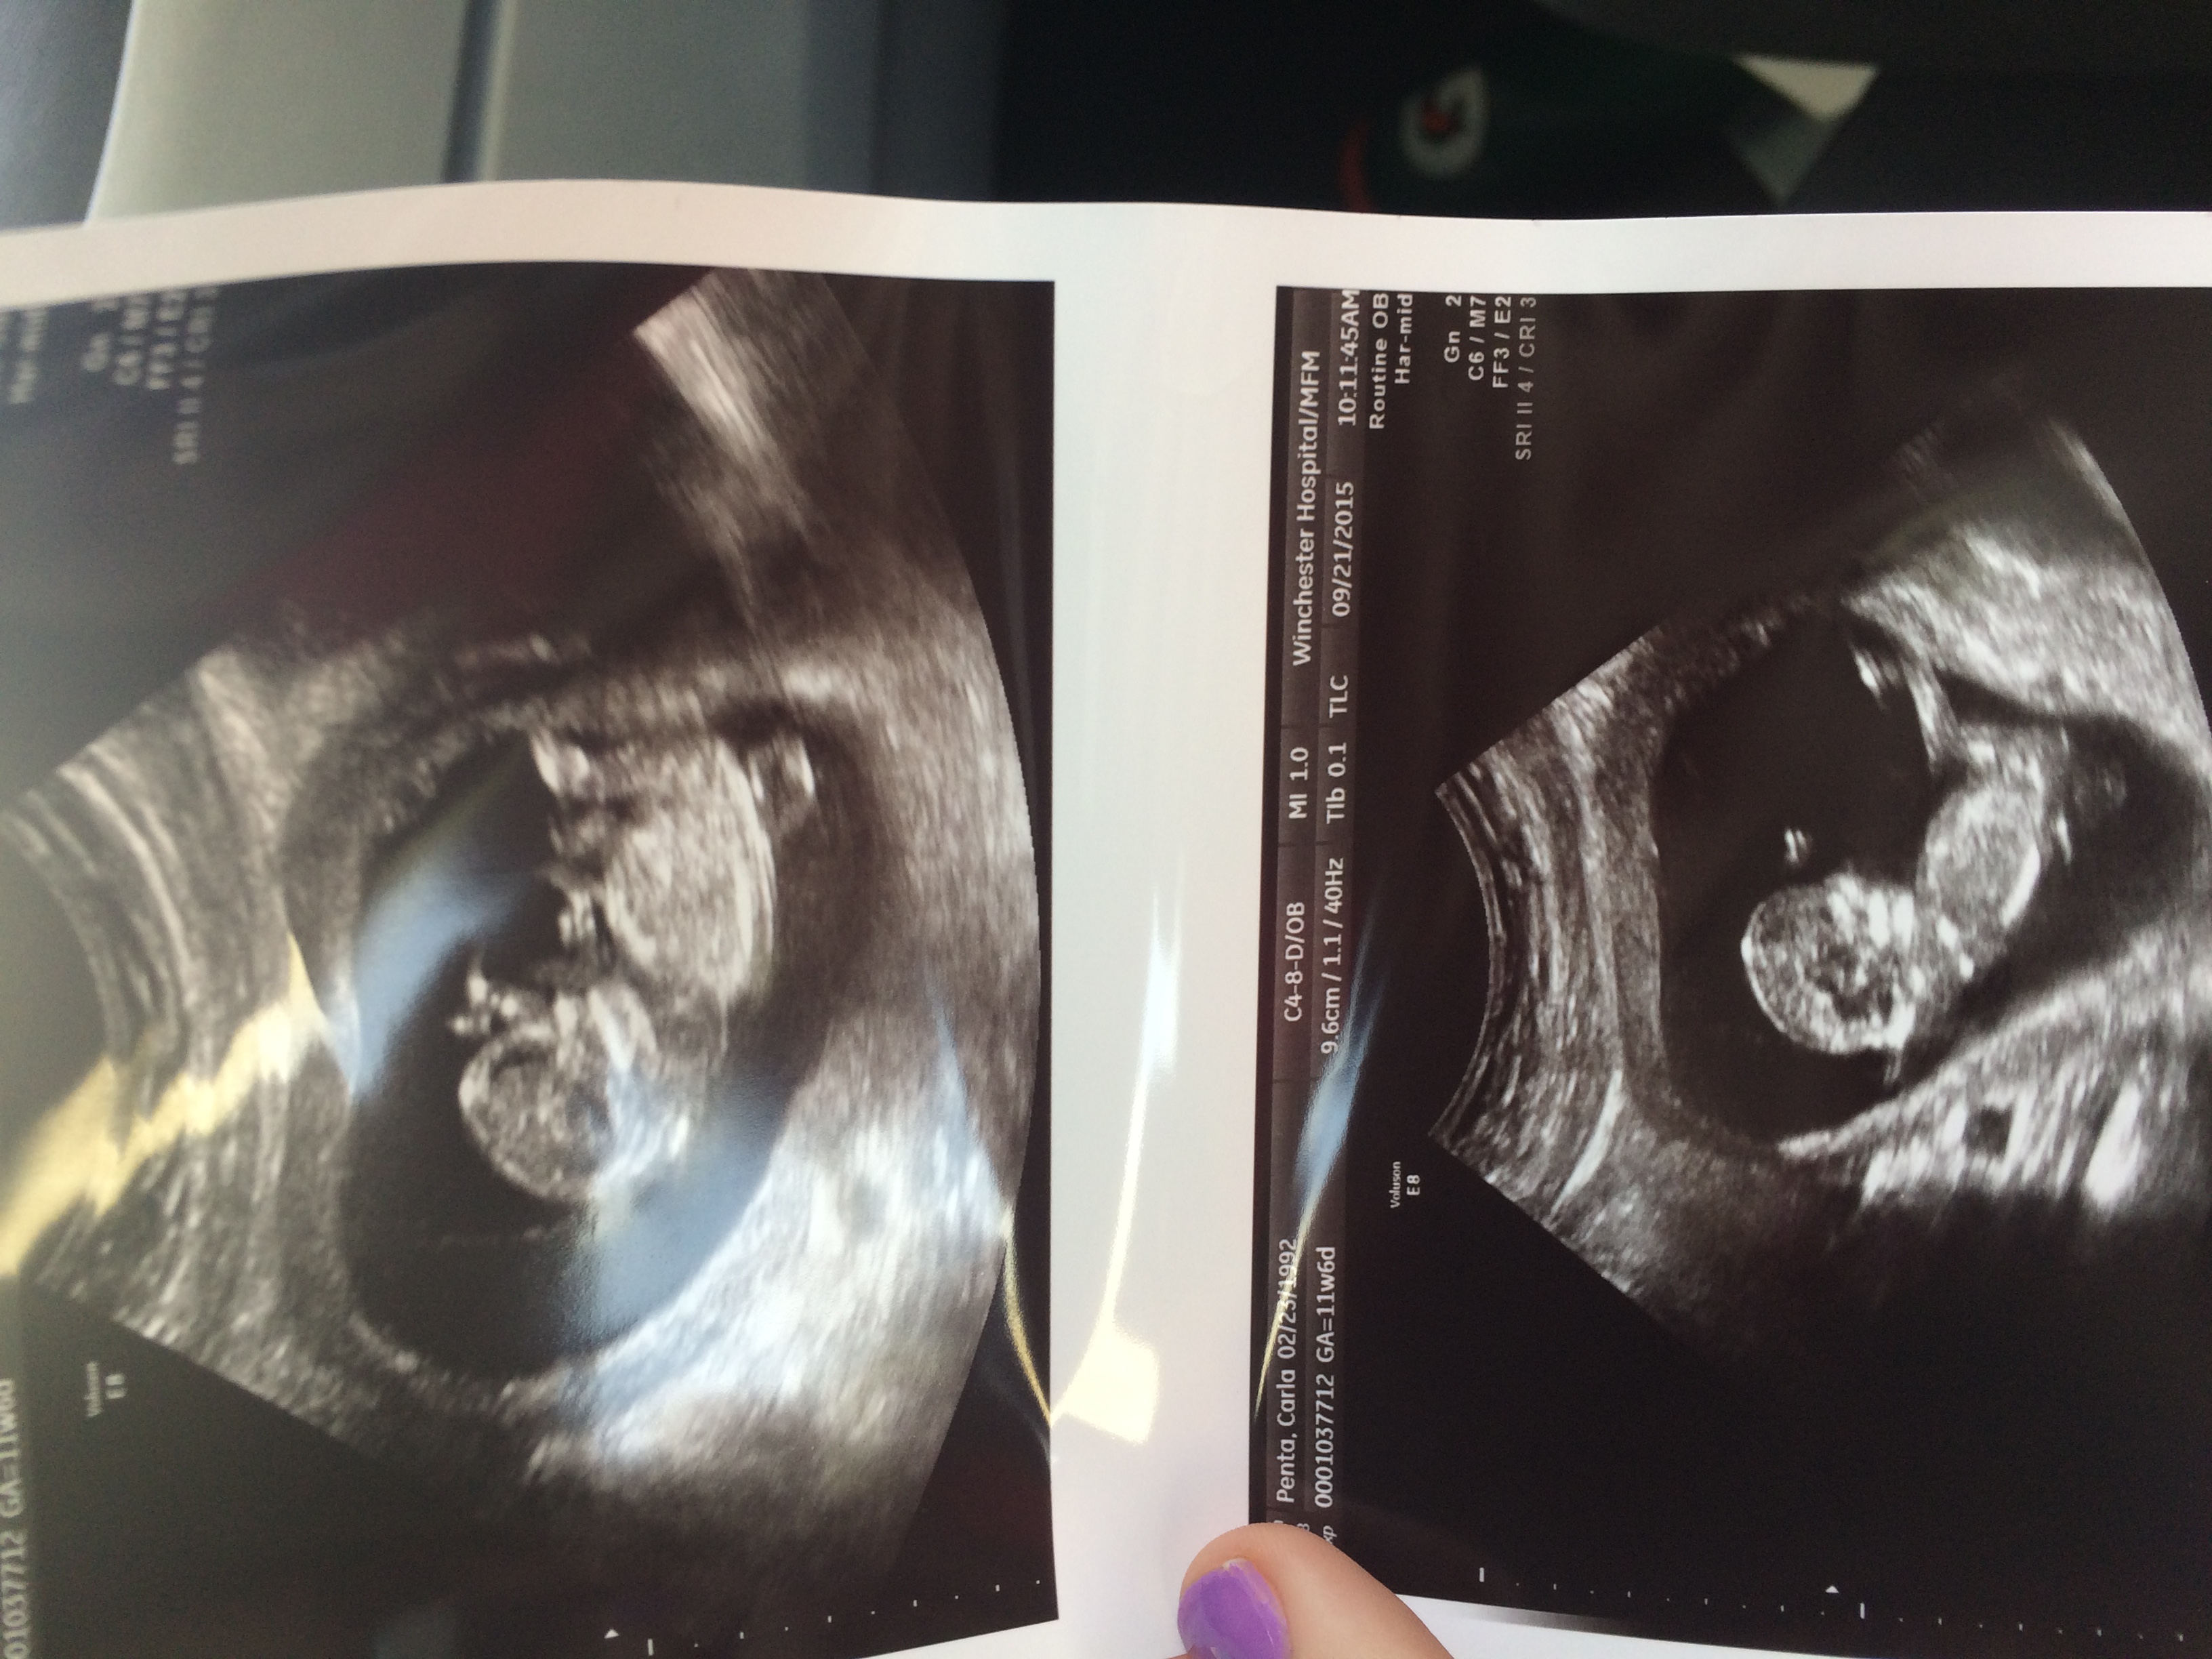

2nd ultrasound yesterday! First one was at 6 w 4 d and this one was at 12 w 4 d! Baby is measuring right smack dab on as far as dating and NT scan looked normal! Saw baby moving its hands and crossing its legs- loved it especially with all the bleeding and spotting scares we had this trimester!!